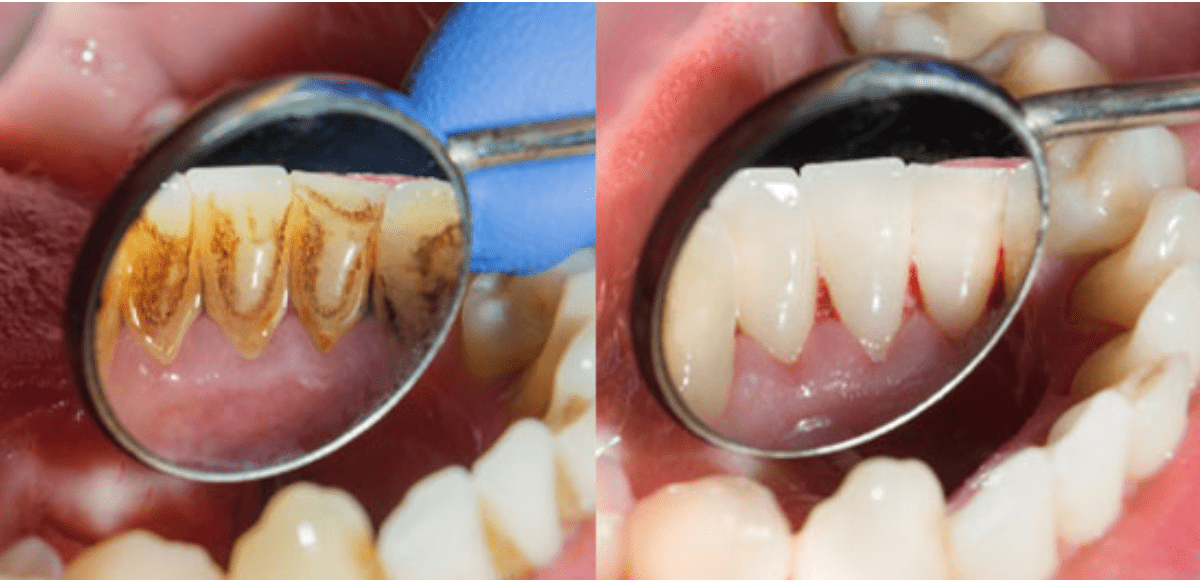

Penyakit Karang Gigi Gejala Penyebab Pengobatan Kompas Com

Cara Menghilangkan Karang Gigi Bisakah Dilakukan Sendiri Halaman All Kompas Com